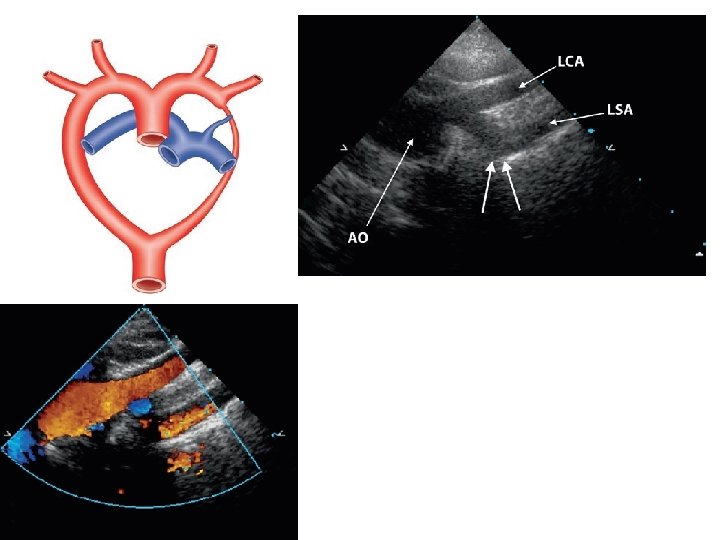

Rt arch with retroesophageal LSCA